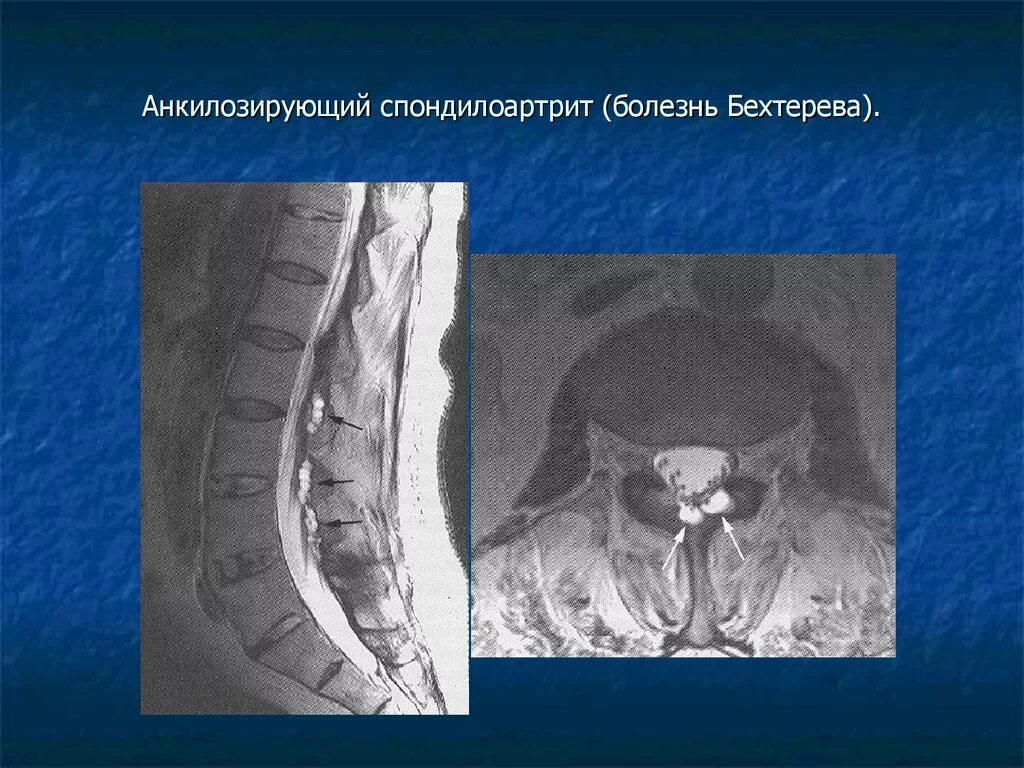

Бехтерева анкилозирующий спондилоартрит